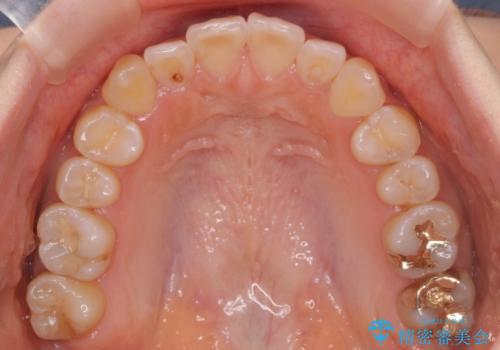

八重歯 インビザラインで抜歯矯正 ただし1本のみの抜歯で済みます

今回は口元も出ていないうえに、右上のみの八重歯のため奥歯を後ろに下げて治療しました。

ただし、下の前歯は入りきらない為1本のみ抜歯しています。

右上の犬歯をおろしてくるのに、顎間ゴムを使用しています。